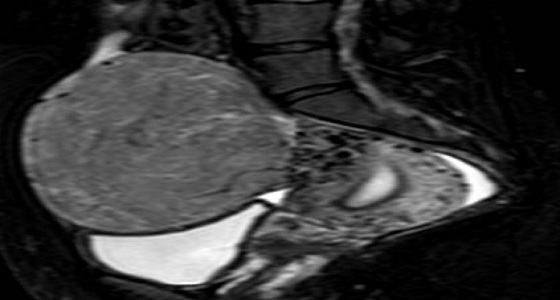

ورم ليفي

استئصال ورم ليفي كبير من حوض مريضة في الرس

فريق طبي بمستشفى بللحمر يستأصل ورم ليفي من فتاة عشرينية